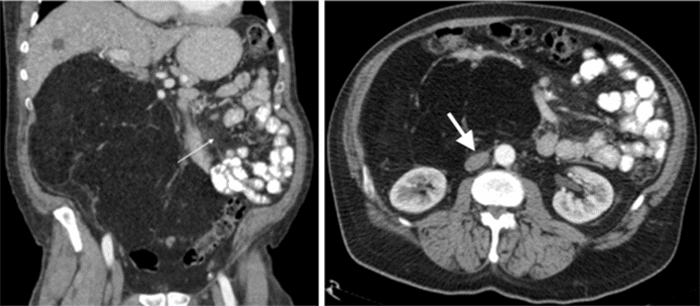

A 57-year-old male presented with right upper quadrant pain radiating to his left side and back. Right upper quadrant ultrasound revealed gallbladder wall thickening, cholelithiasis, and a large retroperitoneal mass. Magnetic resonance cholangiopancreatography (MRCP) confirmed gallbladder wall thickening and cholelithiasis along with a large fatty retroperitoneal mass (Figure 1). Laparoscopic cholecystectomy with intraoperative cholangiogram and core needle biopsy of the retroperitoneal mass was performed at an outside facility. The biopsy showed benign adipose tissue with no malignancy.

Figure 1. Initial MRCP. Published with Permission

Large white arrow: Denotes small bowel compression due to mass effect. Small white arrow: Denotes a large retroperitoneal tumor with internal septations

Imaging diagnosis of PLH is challenging due to its similarity to other lipomatous tumors. However, recent case series, after reviewing all reported cases, suggest some findings that may aid in diagnosis. Most PLHs are well-demarcated cystic and solid lesions exhibiting progressive or late enhancement on contrast-enhanced CT or MRI. They are most frequently located in the pancreatic head or uncinate process. MRI can demonstrate the solid component as iso- to low-intensity on T1-weighted images and iso- to high-intensity on T2-weighted images.¹˒³ FDG-PET demonstrates uptake in approximately 20% of patients, potentially leading to misdiagnosis as pancreatic adenocarcinoma.³ Many of these lesions remain stable over time on serial imaging, unlike the rapid growth observed in our patient.³ Our patient’s MRCP revealed multiple irregular nodular soft tissue densities with increased T2WI signal. Contrast-enhanced CT showed multiple internal septae without progressive or late enhancement but did reveal increased vascularity. The large size of our patient’s mass caused significant mass effect on surrounding organs and vascular structures, making it difficult to assess invasion, a feature distinguishing this case from others.